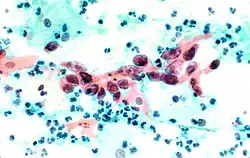

Squamous Cell Carcinoma, bronchial washing. -

Squamous cell carcinoma in the cervix.

The stain should result in cells that are fairly transparent so even thicker specimens with overlapping cells can be interpreted.[2] Cell nuclei should be crisp, blue to black in color[12][13] and the chromatin patterns of the nucleus should be well defined. Cell cytoplasm stains blue-green and keratin stains orange in color.[13][5]

Eosin Y stains the superficial epithelial squamous cells, nucleoli, cilia, and red blood cells.[2] Light Green SF yellowish confers a blue staining for the cytoplasm of active cells such as columnar cells, parabasal squamous cells, and intermediate squamous cells.[14] Superficial cells are orange to pink, and intermediate and parabasal cells are turquoise green to blue.[12]